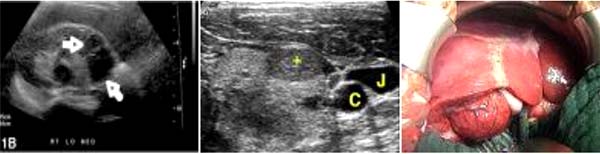

+  !important; Siêu âm bụng có gan lớn nhẹ với nhiều tổn thương giảm âm trong gan;

+  !important; Chụp CT scan cho thấy đa ổ thương tổn không đồng nhất, giảm tỷ trọng, tụy lớn toàn bộ và phản ứng màng phổi nhẹ cả 2 bên

Trong số các công cụ chẩn đoán hình ảnh, siêu âm ít có giá trị chẩn đoán trong pha cấp, trong khi CT scan cản quan có ích trong chẩn đoán. Trên hình ảnh CT có thể phát hiện nhiều loại tổn thương khác nhau: nhiều vùng có nốt một hay nhiều tổn thương giảm âm gây ra do ký sinh trùng ký sinh và gây bệnh, giống abces và dạng đường hầm tựa nhánh cây hoặc đường ngoằn ngoèo giảm tỷ trọng do hậu quả của ấu trùng di chuyển trong nhu mô gan và gợi ý chẩn đoán tốt. Nếu tổn thương là đường ngoằn ngoèo ngoại vị có mặt thì bệnh sán lá gan ở gan là đề nghị chẩn đoán ưu tiên một. Vì khía cạnh lâm sàng và cận lâm sàng của sán lá gan rất dễ nhầm lẫn với nhiều bệnh lý khác, nên tổng hợp một loạt các thông số nghi ngờ để thiết lập một chẩn đoán đúng là cần thiết. Cả siêu âm và CT scan đều có ích trong việc đánh giá theo dõi diễn tiến điều trị bệnh.

Trong một nghiên cứu, các tác giả tìm thấy trong số các bệnh lý phổi màng phổi, thâm nhiễm nhu mô phổi thì thường đi kèm hội chứng Loffler và lan tỏa-đây cũng chính là các đặc điểm chính hay gặp trên Xquang phổi. Đặc điểm X-quang phổi của bệnh sán lá gan lớn trong một trường hợp cũng được mô tả trong một ca liên quan đến phúc mạc là tổn thương giảm tỷ trọng ở mạc treo tràng. Trong khi hình ảnh phim phổi vẫn còn tranh luận thì việc xuất hiện một hình ảnh mới nào liên quan bất thường đến các cơ quan sẽ là một chỉ điểm có ý nghĩa. Ca bệnh trình bày ở đây có thể là báo cáo đầu tiên về bệnh sán lá gan có liên quan và ảnh hưởng lên nhiều cơ quan cùng lúc. Sự di chuyển của sán đến lách và tụy và có lẽ cả thận được xác định qua CT, tuy nhiên phản ứng quá mẫn (hypersensitivity reaction) với kháng nguyên Fasciola cũng có thể liên đới. Xét nghiệm bệnh học xác định các vị trí tổn thương lạc chỗ lại chưa được làm, song sự cải thiện các tổn thương qua theo dõi điều trị là có giá trị khẳng định. Các bệnh nhân có tình trạng miễn dịch suy giảm liên quan đến việc sử dụng thuốc ức chế miễn dịch có thể giải thích phần nào hiện tượng mà ký sinh trùng nhiễm và lan tỏa nhiều cơ quan.